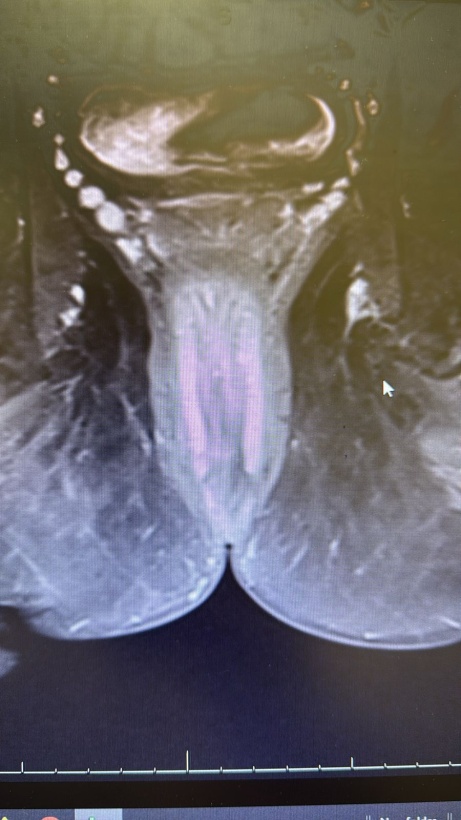

• 3) Imaging: Ultrasound revealed a thickened, edematous scrotal sac with a loculated collection (35 × 10 mm) at the posterolateral aspect, suggestive of cellulitis and abscess formation [3]. MRI confirmed an irregular fluid collection within the corpus spongiosum at the level of the superior pubic ramus, extending to the prostatic urethra with intense enhancement of the soft tissues [4]. Figures 1-3 show the pre operative MRI.

Figure 1. Axial T2-weighted pelvic MRI demonstrating a hyperintense periurethral fluid collection within the corpus spongiosum at the penoscrotal junction, consistent with abscess formation.

Figure 2. Sagittal T2-FS weighted MRI showing extension of the periurethral abscess along the proximal corpus spongiosum without evidence of cavernosal involvement.

Figure 3. Axial post-contrast T1-weighted MRI demonstrating peripheral rim enhancement of the periurethral collection, confirming abscess cavity formation with surrounding inflammatory changes.